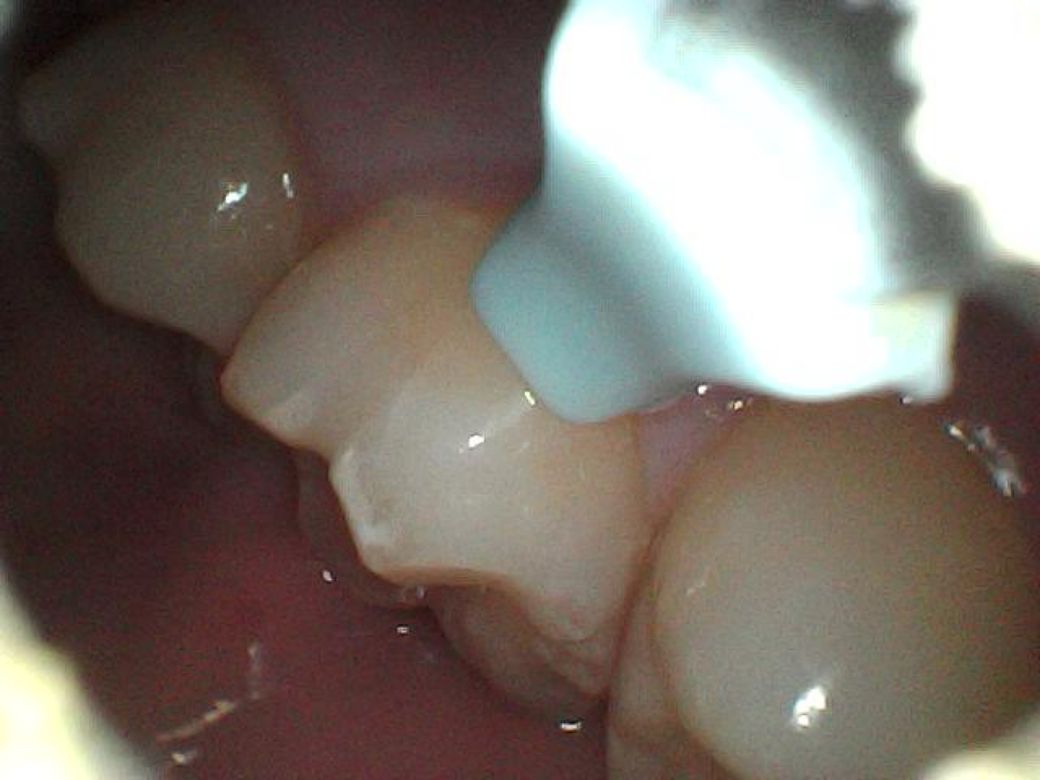

이빨에 뭔가 하얀 것이 생겼어요, 충치인가요?

제가 이

닦고 혀로 스캔하는 버릇이 있는데 그 전까지는 느껴지지 않다가 어제부터 왼쪽 어금니 옆에 만져지는 무언가가 생겼어요.

제가 내시경 귀이개가 있어서 들여다봤는데 치석인지 충치인지 모르겠네요..

혀로 만지는 촉감은 현무암같이 꺼끌꺼끌한 돌덩이 같기도 하고.. 뭔가 부식된 것 같은 촉감도 느껴져요

어제 아침, 오늘 아침 이틀동안 찍은 사진들인데 이거 혹시 사진으로 뭔지 구분이 가능할까요?

처음 두장이 어제, 나머지가 오늘 사진입니다

어제

• 1번 째 사진

• 2번 째 사진